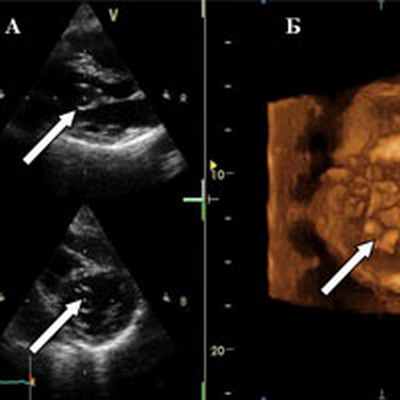

При ЭхоКГ камеры сердца не расширены; глобальная и регионарная систолическая функция левого желудочка (ЛЖ) в пределах нормы; створки митрального клапана тонкие, движение в противофазу. В полости ЛЖ лоцируется четко очерченное округлое двухкамерное тонкостенное образование с эхонегативным содержимым диаметром 30 мм, прикрепленное к подклапанным структурам (хорды, папиллярные мышцы) подвижное, совершающее переднесистолическое движение в фазу сердечного цикла, вызывающее умеренную обструкцию выходного отдела ЛЖ. Диастолическая скорость на МК в пределах нормы. Митральная регургитация не определяется. Заключение: киста митрального клапана неясного генеза (рис. 1).

Рис. 1. ЭхоКГ в двухмерном режиме (A) и в трехмерном режиме (Б). На передней створке митрального клапана определяется тонкостенное полостное образование — киста (указано стрелками).